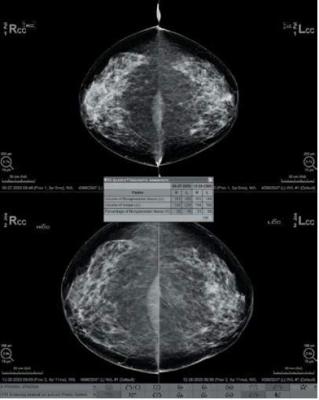

Until recently, consistent assessment of breast composition was hampered by widely differing technical factors and the subjectiveness of the reviewer. The Hologic Quantra volumetric assessment tool is a breakthrough technology that estimates volumes in the breast and calculates the volumetric fraction of fibroglandular tissue. The Quantra tool uses details of the X-ray imaging chain to quantify fibroglandular tissue in the breast. Quantra software aggregates volumetric measurements from each view in a study into a simple, concise assessment for each breast.